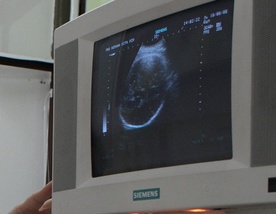

W Polsce wzrasta ilość aborcji, które są efektem badań prenatalnych - wynika ze sprawozdania Rady Ministrów z wykonania oraz stosowania ustawy z 1993 r. O planowaniu rodziny, ochronie płodu ludzkiego i warunkach dopuszczalności przerywania ciąży. O ile w 2002 r. dokonano 82 aborcje z tego powodu, w 2010 było takich aborcji ponad siedmiokrotnie więcej - 611. (Dane za 2010 jeszcze nie zostały ostatecznie opracowane, są to na razie liczby szacunkowe).

Lawinowo wzrasta natomiast liczba aborcji, które są wynikiem wykonanych wcześniej badań prenatalnych – od 2002 r. jest ich ponad siedmiokrotnie więcej – w 2002 było ich 82, w ubiegłym roku aż 611. Tylko w ciągu roku liczba dzieci pozbawionych życia wzrosła o ponad 100 – w 2009 wykonano 510 aborcji, w 2010 – aż 611. Może to świadczyć o coraz większej dostępności tego typu badań.